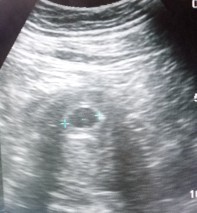

รูปที่1 5w รูปที่ 2-3 6w3d ค่ะ เราไปฝากตั้งแต่ 4w แต่หมอซาวด์ยังไม่เจอน้อง เลยรับฝากตอน 6w3d เจอน้องพร้อมหัวใจเต้นค่ะ

เราซาวด์ตอน6w3dค่ะ หมอซาวด์ทางช่องคลอดเพื่อดูถุงตั้งครรภ์กับตัวอ่อน เจอน้องชัดเจนเลยค่ะ ตื่นเต้นมากๆ☺️

ซาวด์5Wค่ะ ไม่เจอน้องเหมือนกันค่ะ เจอแต่ถุงตั้งครรภ์ หมอยังไม่รับฝาก นัดอีกที 3 พ.ย. จะได้8Wพอดีค่ะ